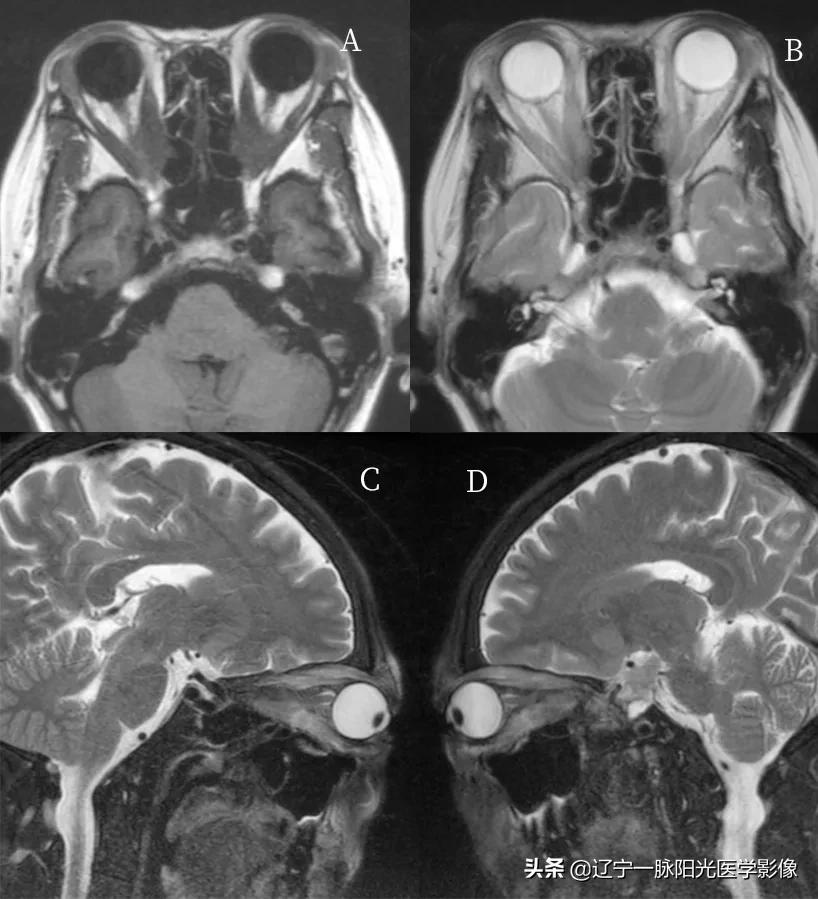

影像所见;:

图 A、B 轴位示右侧眼球稍向前突,球后充盈团块状软策划信号影,范围约 4.3 cm×3.5 cm, T1WI、T2WI 呈低信号

图 C 示 DWI 亦呈低信号

图 E、F 增强后呈不均匀明显强化,其内见环行强化,病灶包绕右侧视神经及眼肌

病理诊断:炎性假瘤